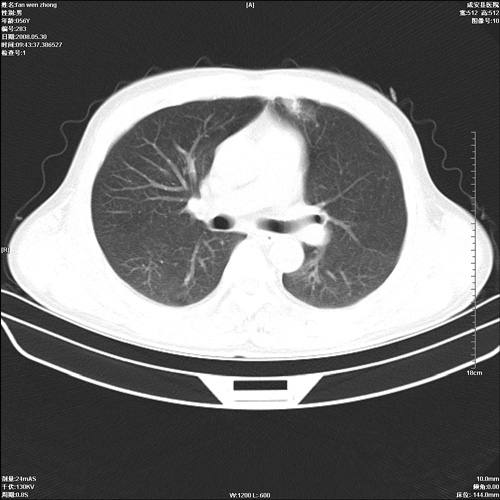

病人 男 56岁 一周前高热,体温达39-40度,经抗炎治疗后,体温渐降,达37,5-38度,轻微咳嗽,胸部不适 查白细胞为1.3万 行ct检查,请分析。

双肺内可见多发结节状病灶,并见小空洞,病人高热,白血球增高,应该是典型的迁徙性肺脓肿(多为金黄色葡萄球菌感染)。查一下口腔等其它部位有无感染灶。

双肺内可见多发结节状病灶,并见小空洞,病人高热,白血球增高,应该是典型的迁徙性肺脓肿(多为金黄色葡萄球菌感染)。建议治疗后复查.